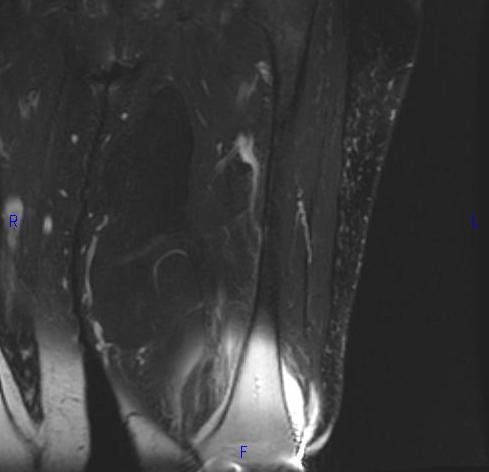

MRI (Fig. 1, 2, 3 and 4)

• Large encapsulated lipomatous mass. (Fig. 1, 2, 3 and 4)

Fig. 2-4 MRI: Coronal T2-weighted fat suppressed (Fig. 2) and Axial T2-weighted FS (Fig. 3) shows low intensity signal isointense with fat. Adypocitic lesion with fatty signal is located in the posterior and medial compartment of the thigh. Thickened septa and nodularity enhances on post contrast images. (Fig. 4)